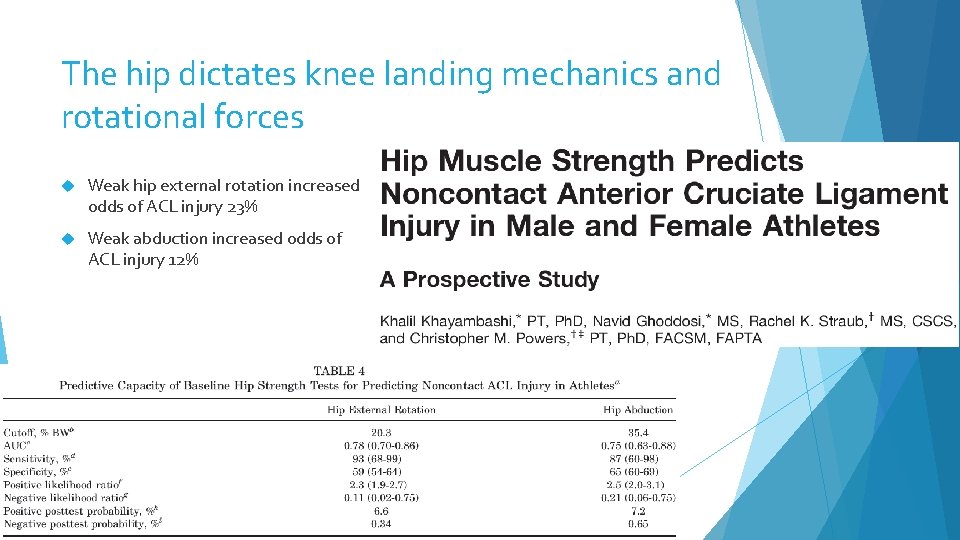

The hip dictates knee landing mechanics and rotational forces Weak hip external rotation increased odds of ACL injury 23% Weak abduction increased odds of ACL injury 12%